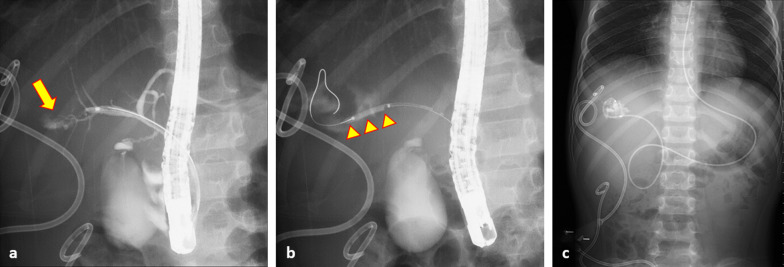

We continued to evaluate the hepatic injury using abdominal ultrasonography and CT. The patient experienced abdominal distension caused by ascites fluid and right lateral abdomen pain 18 days after injury. An abdominal drain was inserted at the site of lateral abdomen pain. Abdominal ultrasonography revealed fluid collection in the right infradiaphragmatic region. He had high total and direct bilirubin levels and was diagnosed with a biliary fistula, with more than 400 mL of fluid drainage per day. Magnetic resonance cholangiopancreatography revealed injury to the posterior branch of the bile duct 25 days after the injury. The biliary fistula showed poor improvement with percutaneous drainage. Endoscopic nasobiliary drainage (ENBD) was performed using endoscopic retrograde cholangiopancreatography (ERCP) after bile duct dilatation 59 days after the injury (Fig. 3). The volume of bile drained through the percutaneous drainage tube was approximately 400 mL/day for the first 2 weeks, and about 100 mL/day thereafter. After ENBD implantation, the volume gradually decreased. At the time of discharge from the hospital, almost no drainage was observed. The patient had no neurological sequelae and was discharged from the hospital 102 days after the injury. The drain was removed during an outpatient visit after cessation of the bile leak.

Fig. 3.

Abdominal X-ray. a Cholangiography using ERCP shows the bile leak from the bile duct of B6 (yellow arrow). b Bile duct dilatation using the balloon of 3 mm in diameter (yellow arrowheads). c Endoscopic nasobiliary drainage (ENBD) and percutaneous drainage of the traumatic biliary fistula at the right subdiaphragmatic and subhepatic regions